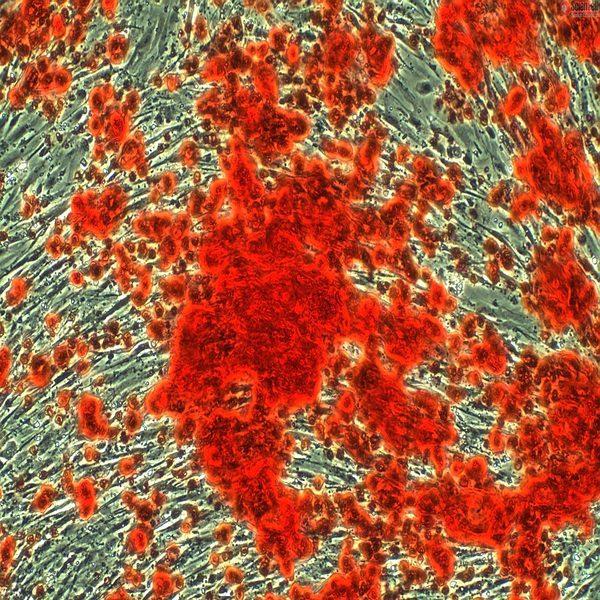

- Examination of cell placement on tissue scaffolds with SEM microscopy

On the other hand, in cutting-edge sciences such as tissue engineering, the use of up-to-date techniques for section preparation and cell tracking and engineered tissue structure has contributed significantly to the development of new studies.